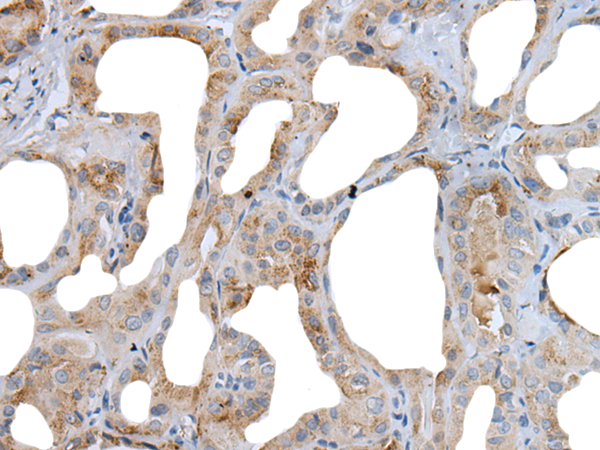

分类: 科研抗体货号: P12768别名: MK3; HGK5; HLK3; PCN3; HPCN3; KV1.3; HUKIII应用: IHC反应种属: Human, Mouse, Rat